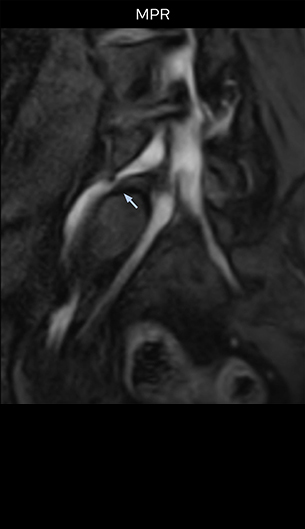

“The intra-luminal signal of veins, especially around the intervertebral space, can be suppressed well with NerveVIEW. As a result, we can easily observe the detailed nerve structure around the posterior ganglion,” he says. “This is why we use 3D NerveVIEW for intraforaminal stenosis and extraforaminal stenosis/herniation (lateral disc herniation). On the other hand, if herniation is suspected to exist inside the dorsal root ganglion (DRG), balanced TFE or ProSet-FFE is applied. NerveVIEW is not suitable for evaluating the median type of herniation.” The SE-EPI DWI-based method for MR neurography works well for large FOV exams like whole-body MRI, but focal examination of nerves is often limited by the attainable spatial resolution (both inplane and slice direction) and geometric distortion. “3D NerveVIEW achieves higher in-plane resolution – close to our other routine spine sequences – and the source images can be used instead of adding a fat-suppressed T2-weighted sequence,” Tanji says.

According to Tanji, methods such as ProSet FFE, STIR or 3D VISTA are anatomically nonselective because background signals, for instance from blood vessels, often interfere with nerves, which hampers evaluation of details, especially at the peripheral side of the nerves.

“Recently, the two surgical methods extreme and oblique lateral interbody fusion (XLIF and OLIF) have become mainstream for minimally invasive treatment of lumbar spinal canal stenosis and intervertebral foramen stenosis. With these surgical techniques, the spine is approached from the flank, and prior knowledge of the exact anatomy of the lumbosacral plexus would be extremely helpful. To that end, high slice resolution (less than 1 mm acquisition) that enables sharper sagittal MPR images will be needed.”

“For both brachial and lumbar plexus, we are currently using a 230 mm FOV and voxels of about 1 x 1 x 2 mm acquired (1 x 1 x 1 mm reconstructed). This provides us a good representation of the nerves, even though this FOV is relatively small. Regarding the inplane resolution, we hope to be able to bring that down to 0.7 mm, similar to our typical 2D multislice T2W images,” says Tanji.